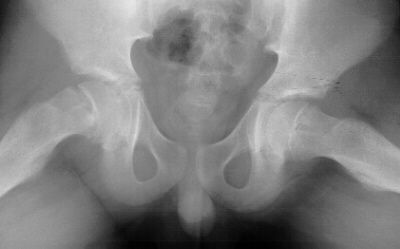

What is the evidence for screening DDH

No evidence to screen

Imaging prior to 6 months in infants with clinical evidance, fam hx, breech,